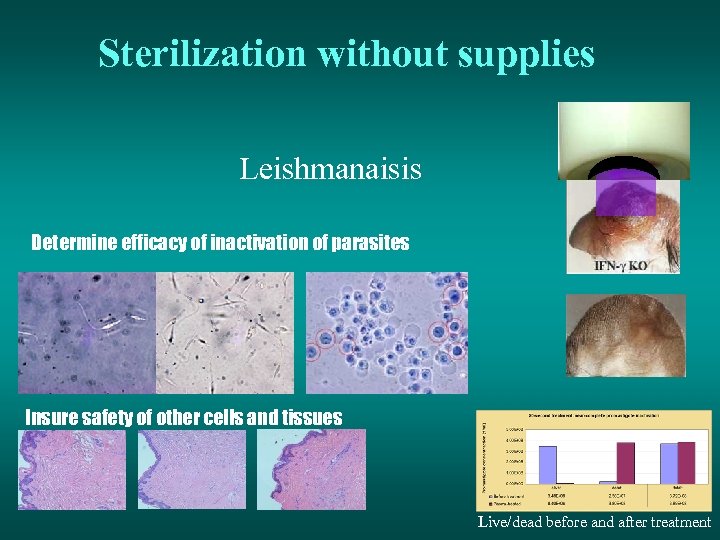

Sterilization without supplies Leishmanaisis Determine efficacy of inactivation of parasites Insure safety of other cells and tissues Live/dead before and after treatment

Sterilization without supplies Leishmanaisis Determine efficacy of inactivation of parasites Insure safety of other cells and tissues Live/dead before and after treatment